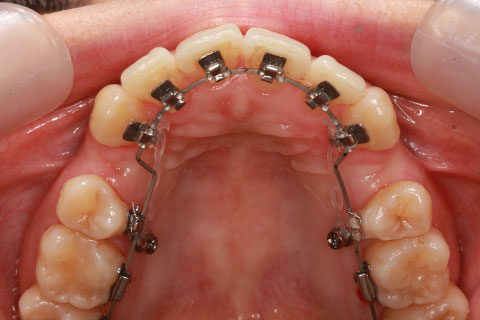

矯正期間24ヶ月

ハーフリンガル矯正3(上の歯のみ舌側矯正で治療)

治療前

治療中(開始直後)

治療中(開始半年後)

治療後

- 年齢・性別

- 25歳女性

- 治療期間

- 2年0ヶ月

- 抜歯

- 上下4番抜歯

- 治療費

- 110万円

- 備考

- 治療内容

- 施術の副作用(リスク)

- 表側矯正と比較して、力学的な操作性が複雑なため、ボーイングエフェクトを起こしやすい。